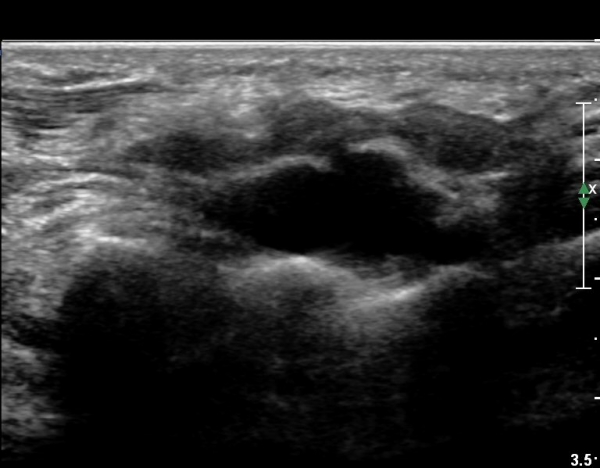

4 sono.jpg

¼Õ¹Ù´Ú ºÎÀ§¿¡¼­ ô°ñ½Å°æ ½ÉºÎ °¡Áö º´Áõ

(periphral neuropathy  of  deep palmar branch of ulnar nerve at palm level).